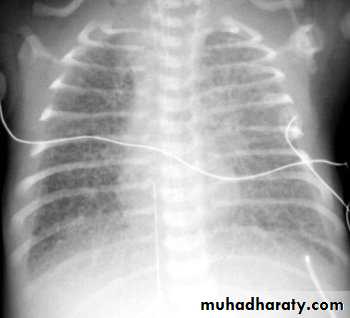

CXR will also reflect the amount of pulmonary blood flow